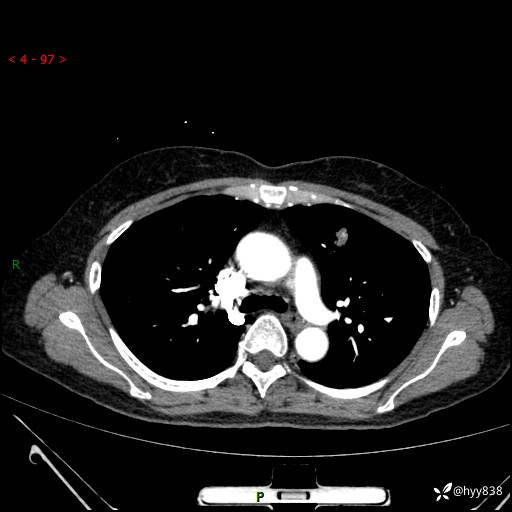

54岁/女,发现肺占位1天。观其形态和强化,术前我信心十足,术后我---结果公布~

【患者信息】:54岁/女

【主诉】:发现肺占位1天

【现病史及既往史】:患者2023.10.23体检发现肺占位:,2023.10.23当地区中心卫生院胸腹部CT:1.左肺上叶结节,考虑为占位可能;2.肝脏小囊肿灶;3.子宫左侧附件区畸胎瘤;无咳嗽咳痰,无恶心呕吐,无发热,无胸闷胸痛等不适;现患者为求进一步诊治来我院,门诊以“肺占位”收入我科。 患者自起病以来,精神饮食睡眠一般,大小便正常,体力体重无明显下降。

【检查】:胸部CT增强(外院平扫)